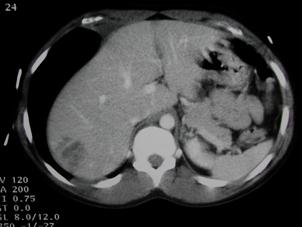

Traumatism abdominal inchis Traumatism

abdominal inchis

Leziune hepatica intraparenchimatoasa Leziune de lob drept

hepatic